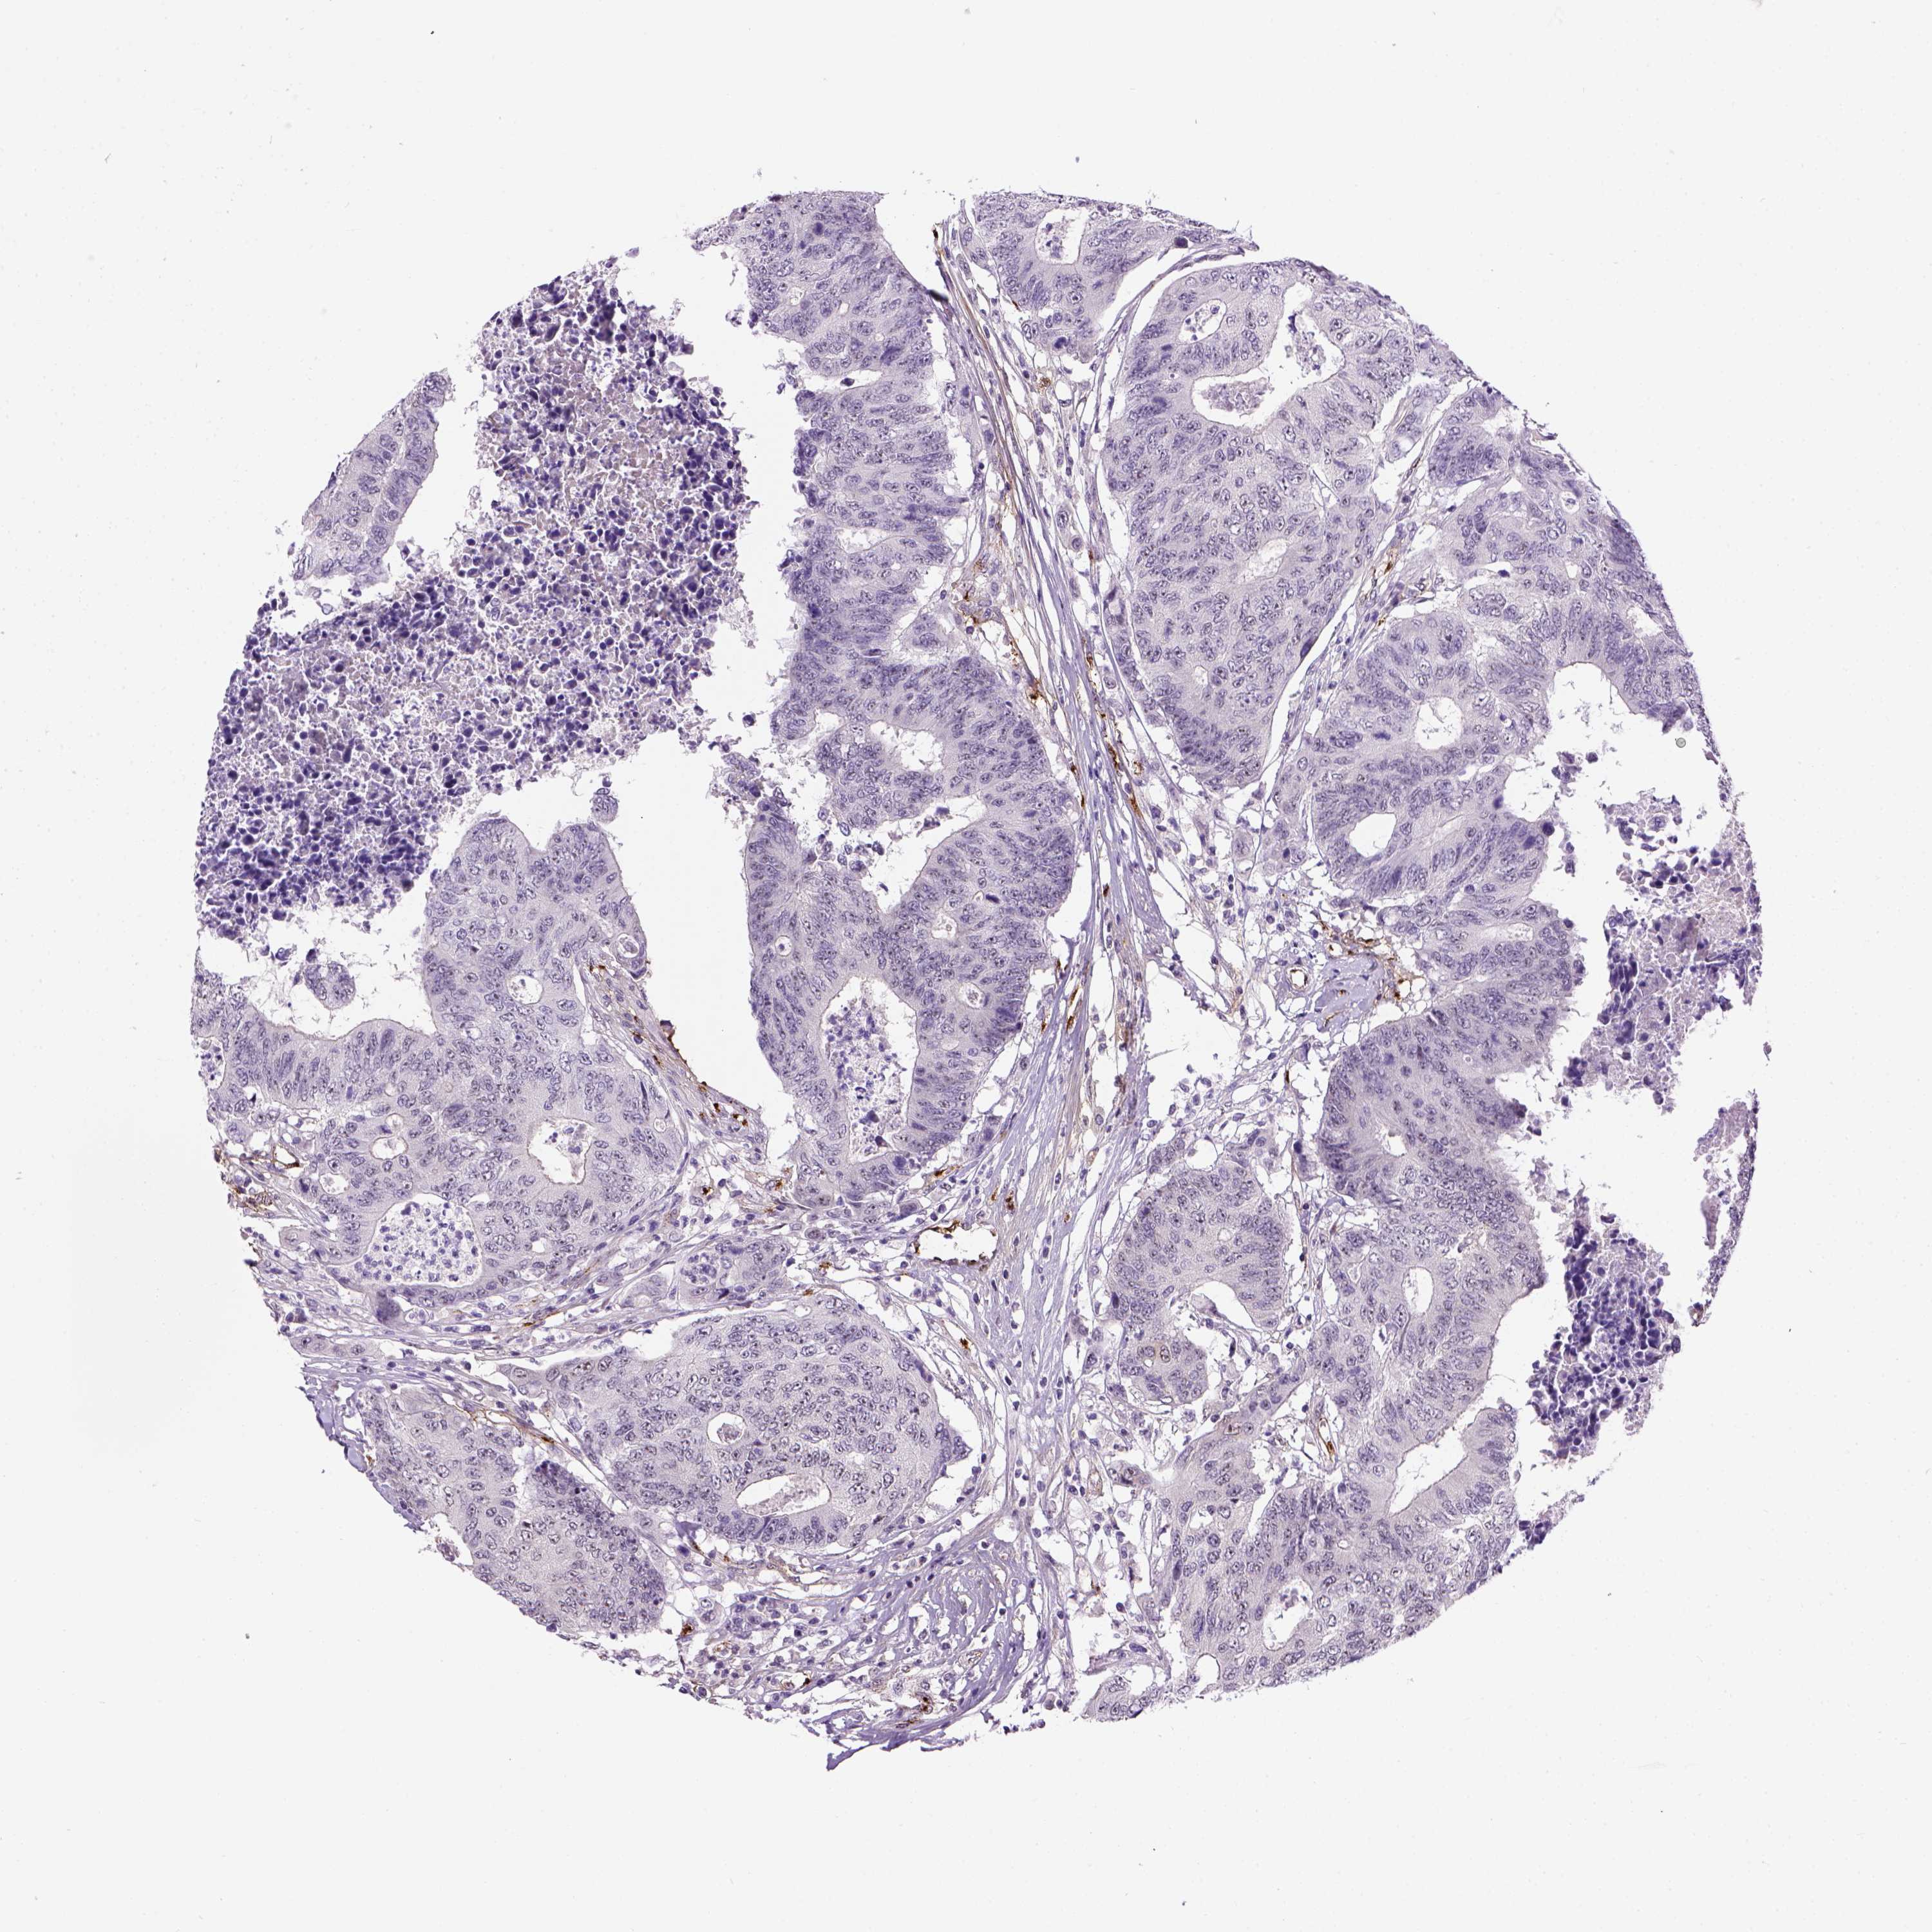

CANCER COLORECTAL CANCER Show tissue menu

COAD TCGA COAD VALIDATION READ TCGA READ VALIDATION PROTEIN COAD CPTAC PROTEIN EXPRESSION

ANTIBODIES

AND

VALIDATION